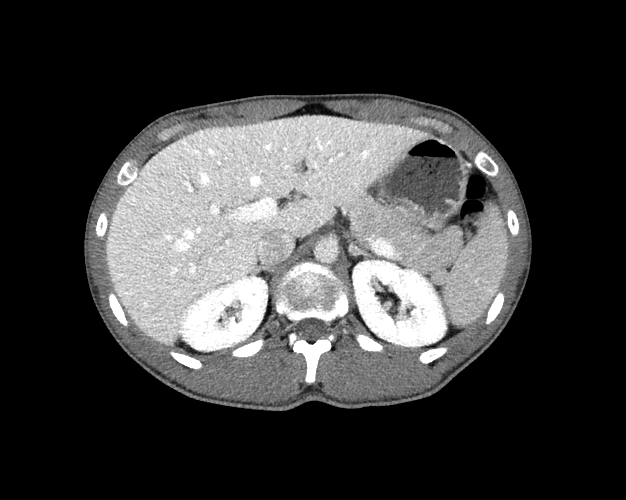

Body

Covers abdominal CT anatomy.